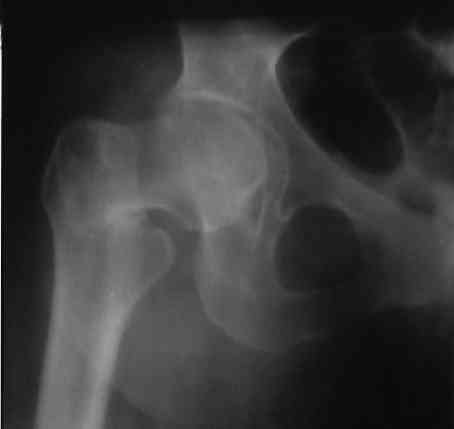

коллеги, отправляю снимок,раньше не получилось.

кто даст какой совет по остеосинтезу в свете остеопороза и рассеянного склероза?Я планирую синтез либо двухугловой пластиной,либо-130 градусной пластиной DHS,PFN просто нет И их приобретение не предвидится

Похоже на базальный перелом, при котором PFN является противопоказанием, а DHS тоже может не всегда привезти к успеху из-за риска вырывания винта. Но так как полной нагрузки не придвидется вселедствие тетрапареза, выбрал бы DHS. Или углообразную пластинку на худой конец.

Уважаемый Дмитрий!Мало информации для корректного совета. Какой уровень самообслуживания больной до травмы? Гипер или гипотонус мышц? Степень выраженности атаксии? Механизм травмы? На личном незначительном опыте (3-4 человека) - заживление ран обычное. Вероятность сращения перелома на данный момент не важна, необходима стабилизация отломков с целью ранней активизации больной. Даже если вы откажитесь от оперативного лечения, активизировать надо больную "вчера". Динамические системы лучше но, при их отсутсвии, можно применить и обычную угловую пластину. У данного перелома несколько больше шансов для сращения чем у медиального или субкапитального.

P.S. Я очень сомневаюсь в выраженном остеопорозе у данной больной, а вот по поводу перекладывания головной боли на анестезиологов - согласен на все сто!